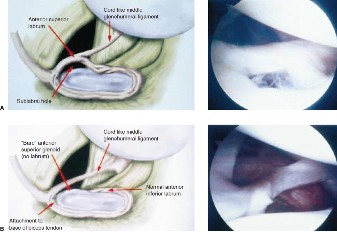

The correct answer is (B). This arthroscopic finding described is a Buford complex (Fig. 2–23B), and it is a normal anatomic variant that occurs in about 1.5% of shoulders. It consists of a cord-like middle glenohumeral ligament (MGHL) that attaches to the biceps anchor with a lack of labral tissue at the anterosuperior glenoid rim. If a Buford complex is misdiagnosed as a SLAP tear and the MGHL were anchored to the glenoid rim (Answer A), the patient could have significantly restricted range of motion, especially in external rotation.

Figure 2–23_Two normal variants of labral anatomy. A, Top: sublabral foramen at 2 o’clock position. B, Bottom: Buford complex. (From Mileski RA, Snyder SJ. Superior labral lesions in the shoulder: pathoanatomy and surgical management. _J Am Acad Orthop Surg. 1998;6(2):121–131.)

Other normal variants found in the shoulder that should be known include a sublabral foramen (Fig. 2–23A) at about 2 o’clock position on a right shoulder that occurs in about 3.3% of shoulders and a sublabral foramen with a cord-like MGHL that occurs in about 8.6% of shoulders. Another normal variant is a meniscoid superior labrum in which the inner lip of the labrum partially covers the glenoid articular cartilage. True SLAP tears can be differentiated from these normal variants because they show hemorrhage or granulation tissue at the base of the biceps tendon or under the labrum, and there is a space between the glenoid articular cartilage and the superior labrum/biceps tendon that can be mobilized 3 to 4 mm with traction of the biceps tendon. Objectives: Did you learn...? Diagnose a SLAP tear through imaging? Classify SLAP tears?